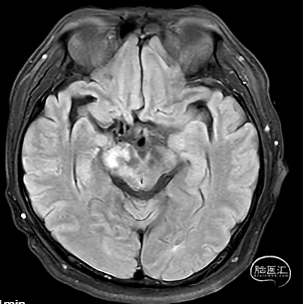

外院CTA示:

1.右侧大脑脚-右侧丘脑急性脑梗死。

2.右侧大脑后动脉P1、2段显影差,P3及其以下未见显影;建议结合临床。

3.结合CTA,符合右侧颈内动脉C7、基底动脉末端动脉瘤。

右侧中脑-丘脑可见新发脑梗塞:

颅内外血管未见明显狭窄。